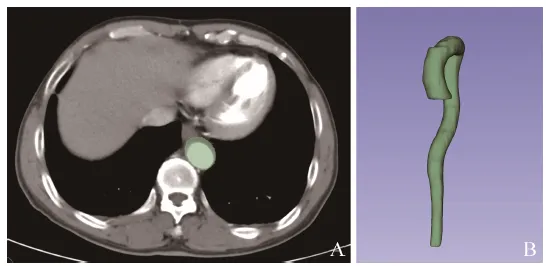

使用3D Slicer 5.2.2软件(www.slicer.org)手动勾画ROI。采用线性插值法将图像标准化为1 mm×1 mm×5 mm。因本研究重点关注主动脉形态和变化,ROI勾画范围包括全程胸腹主动脉(从升主动脉起始至髂动脉起始水平),仅勾画主动脉主干,未勾画主动脉分叉(图1)。由1名具有3年工作经验的放射科医师进行ROI分割,在横断面上逐层半自动勾画ROI,在冠状面和矢状面上进一步完善和修改。使用3D Slicer中的Radiomics插件(版本号:aa418a5)提取影像组学特征,共得到851个影像组学特征,包括形状特征、一阶特征、纹理特征(如灰度共生矩阵、灰度区域大小矩阵、灰度游程矩阵、邻域灰度差矩阵、灰度依赖矩阵等)和744个小波特征。为确保影像组学特征的稳定性,由另1名放射科医师对45例患者图像(38%)进行ROI分割。保留组内相关系数(ICC)>0.8的特征,以增强模型的稳定性。将119例患者按7∶3分为训练集84例和测试集35例。使用最小绝对收缩与选择算子算法在训练集中进行特征选择。通过十折交叉验证,确定最小λ值,从而识别最优影像组学特征并评估其系数。计算每例患者的影像组学评分,通过Logistic回归分析构建影像组学模型。

图1  横轴位CTA图像示手动逐层沿病灶边缘勾画ROI(绿色区域,A)与分割ROI后生成的3D示意图(B)。CTA为CT血管成像,ROI为感兴趣区